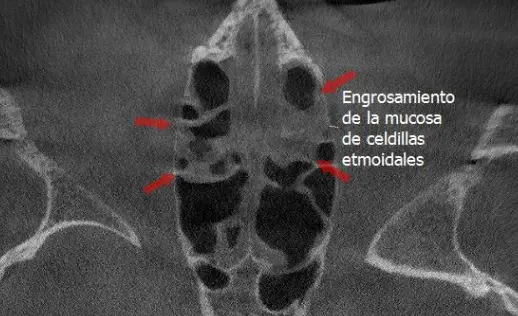

TOMOGRAFÍA PARA SENOS PARANASALES

Preciso para diagnosticar sinusitis, pólipos, obstrucciones, fracturas o tumores, ya que muestra huesos, mucosas y secreciones, y ayuda a planificar cirugías